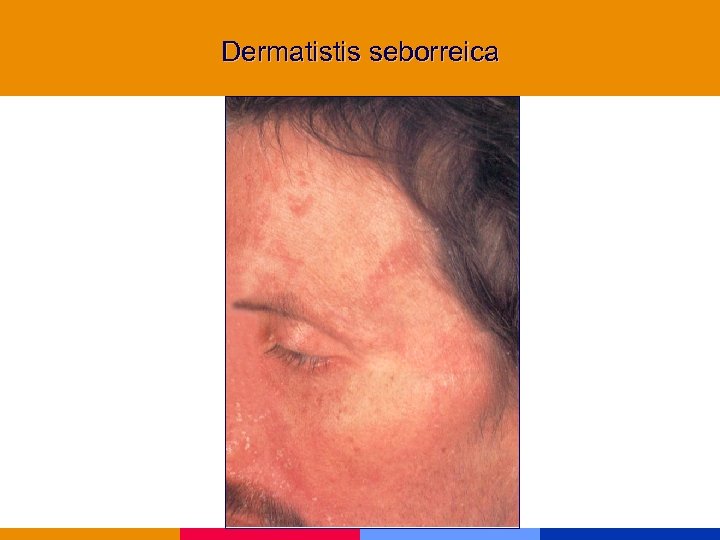

Dermatistis seborreica

Dermatistis seborreica